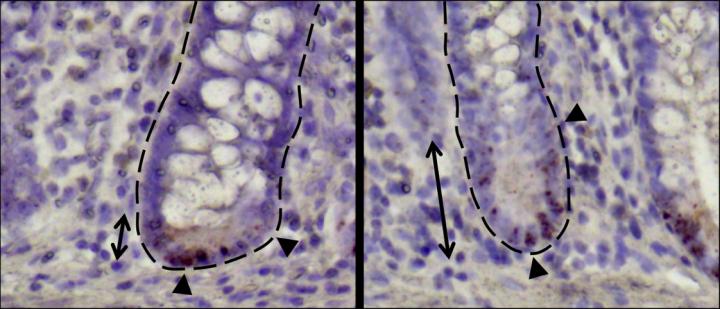

Small intestinal crypts of Crohn´s disease patients.

image: Small intestinal crypts of Crohn´s disease patients. view more

Credit: Prof. Dirk Haller / TUM

Patients suffering from Crohn's disease have fewer Paneth cells and furthermore, these are limited in their functionality. The research group examined the causes for alterations in Paneth cells and attempted to determine the importance of stem cell metabolism in this context.

The study showed that microscopic alterations in stem cell niche were particularly prevalent in those patients who showed symptoms of a relapse of inflammation after six months.